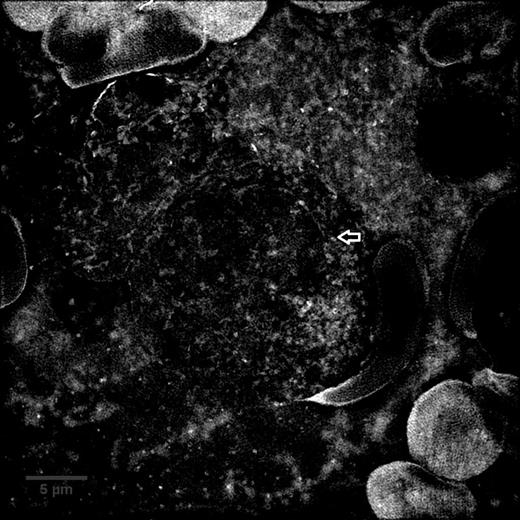

Granular B-ALL bone marrow aspirate sample imaged with SIM and converted to a maximum intensity Z projection, arrow indicates a granule

We took images of the same cells using both brightfield light microscopy and SIM. Figures 2 and 3 show the same cells imaged with both microscopes. We made maximum intensity Z projections (the pixels in stack of images with maximum intensity projected onto one image), cutting off Z-slices where the cell was not focused in order to avoid measuring granules outside the cell. Next, we randomly selected granules to measure in each cell's Z projection. Using Image J software, we measured the surface area, diameter, depth, intensity relative to background, and shortest distance to nucleus and plasma membrane for each individual granule. We then averaged the measurements from each type of sample (granular B-ALL, AML, non-leukemic).

The granules in B-ALL had an average diameter of .285 micrometers, average depth of .506 micrometers, average surface area of .147 micrometers squared, and were on average 2.74 times more intense than the background. The granules in AML had an average diameter of .479 micrometers, average depth of .440 micrometers, average surface area of .2255 micrometers squared, and were on average 1.953 times more intense than the background. The B-ALL granules were smaller and more intense. The stain used for the cytoplasm, eosin, is acidic. The brighter B-ALL granules suggest that they have higher concentrations of basic proteins than the AML granules. This technique may be useful in separating granules in AML leukemia, ALL leukemias, and possibly leukemias of ambiguous lineage.